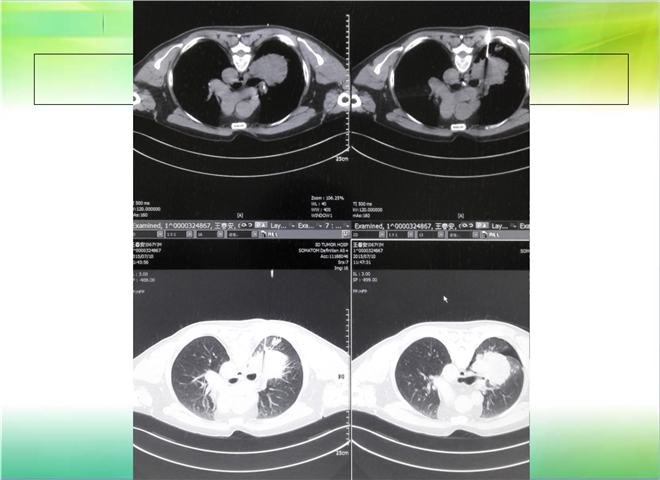

CT引导下穿刺活检术